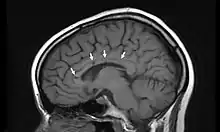

IRM d'une patiente atteinte du syndrome de Susac montrant les « trous » du corps calleux associés à la régression des symptômes (flèches).

L'IRM cérébrale montre des anomalies de la substance blanche ainsi qu'au niveau du corps calleux[4].